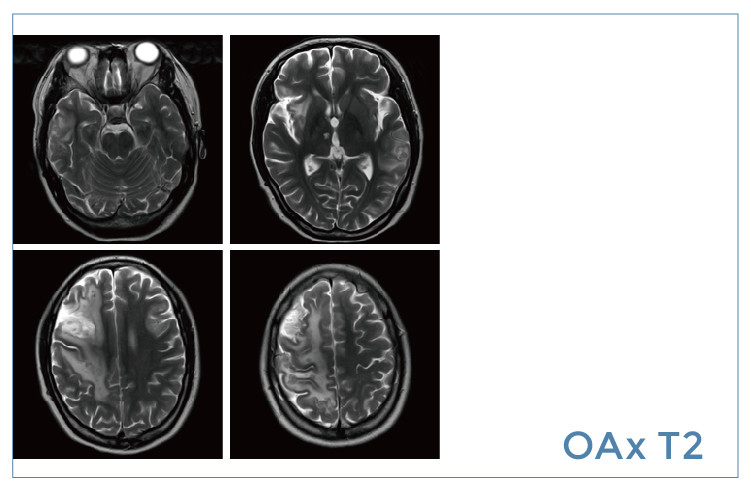

【朗润影像档案】磁共振影像病例分享(编号20200104)